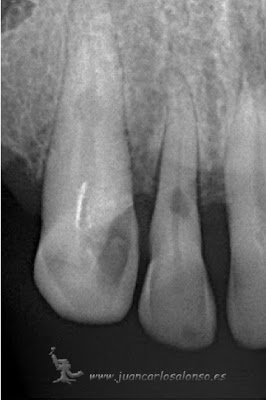

Paciente con cirugía programada para la extracción de los cuatro incisivos inferiores e injerto oseo por presentar un gran quiste a nivel mentoniano. acude a consulta demandando una segunda opinión. las pruebas de vitalidad dan como resultado qué solo el 42 está afectado. se propone ,y acepta, como tratamiento desvitalización del incisivo lateral inferior derecho